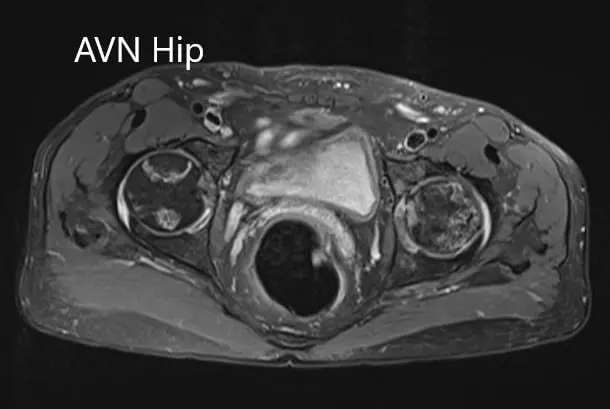

The left femoral head was collapsed with irregular contour and shows areas of altered signal intensity with a line of demarcation. Hypointense areas both on T1WI & T2WI seen in head suggestive of sclerosis. Surrounding marrow edema seen. A small amount of joint effusion with few osteophytes seen. The joint space was preserved.

The right femoral head shows areas of altered signal intensity with serpiginous demarcation line visualized, Hypointense areas both on T1WI & T2WI seen in head suggestive of sclerosis. The femoral head contour was normal. Surrounding marrow edema is seen. Small joint effusion is seen. Joint space is preserved.

Percentage necrotic areas in bilateral femoral heads are approximately 60-70 %.

Axial sections of the T1WI and T2WI of MRI.